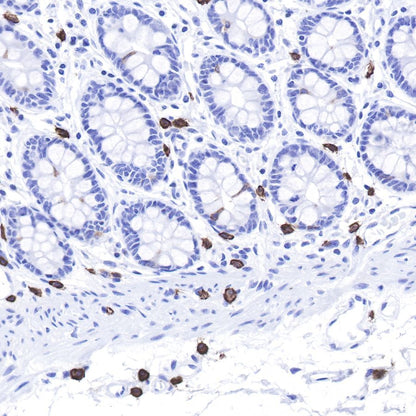

IHC shows positive staining in paraffin-embedded human colon.

Anti-CD117 antibody was used at 1/1000 dilution, followed by a Goat Anti-Rabbit IgG H&L (HRP) ready to use.

Counterstained with hematoxylin.

Heat mediated antigen retrieval with Tris/EDTA buffer pH9.0 was performed before commencing with IHC staining protocol.